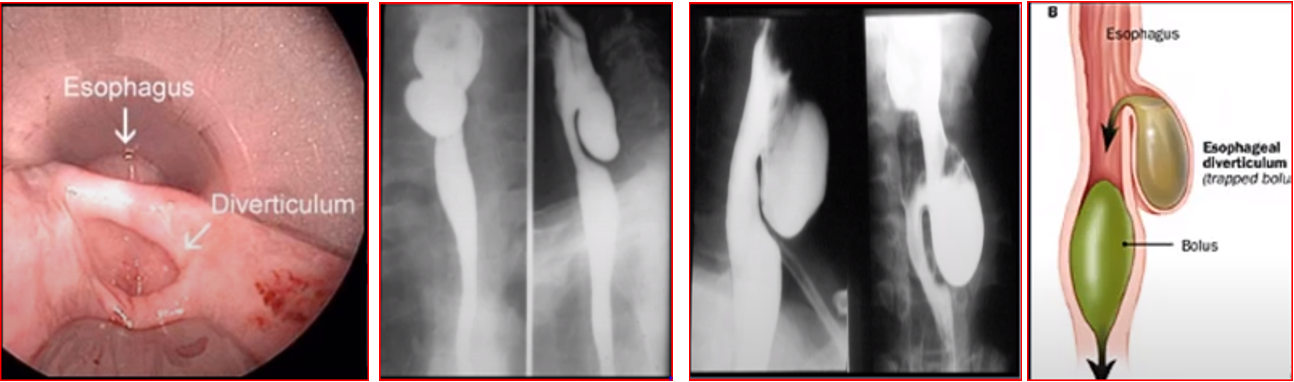

Thin Barium Swallow – Evidence of pouch

Esophagoscopy - not indicated - may result in perforation

outpouching